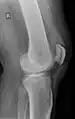

Quadriceps tendon rupture in plain X-ray

X-ray of a tear of the patellar tendon. On the left: The kneecap is pulled up. On the right: Significant dent in the soft tissue above the kneecap.